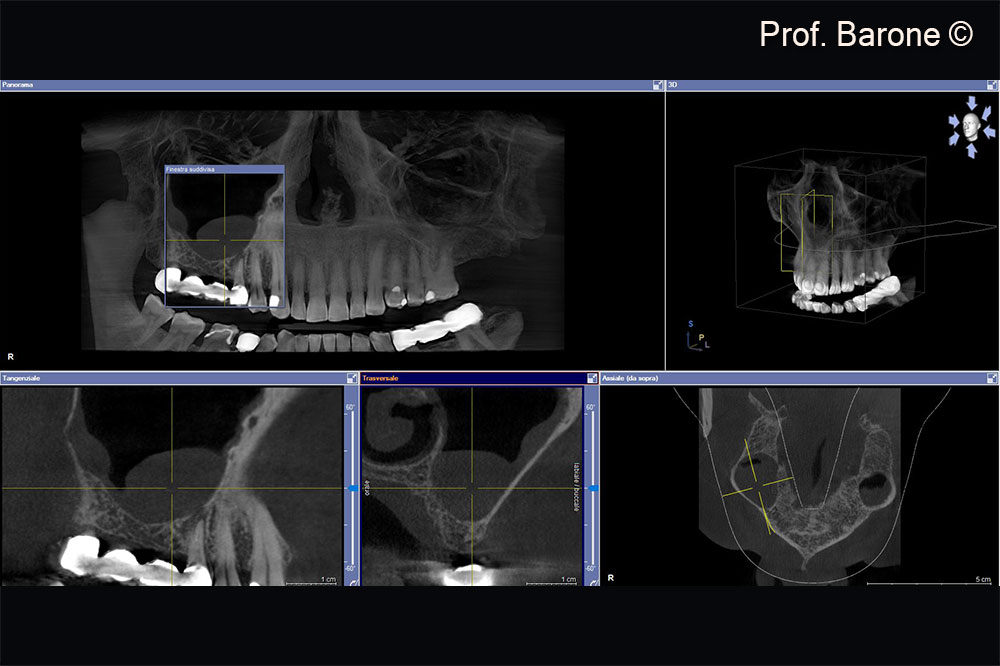

X-Ray examination 7 months after Sinus Lift